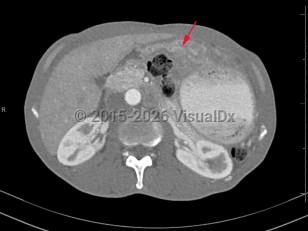

Gastric cancer arises from malignant transformation of gastric cells. Eighty-five percent of gastric cancers are gastric adenocarcinomas; there are other subtypes of gastric cancer that more rarely occur (eg, mucosa-associated lymphoid tissue lymphoma, leiomyosarcoma, gastrointestinal stromal tumors, linitis plastica, gastric adenocarcinoma and proximal polyposis of the stomach [GAPPS]). Histologically, gastric cancers are defined as either intestinal or diffuse. Although gastric cancers can occur anywhere in the stomach, there are epidemiologic differences between tumors that originated in the cardia and tumors with noncardia origins. The rates of gastric cancer have been declining since the identification and treatment of Helicobacter pylori.

Many patients with early, superficial disease are asymptomatic. As the disease progresses, patients may present with vague upper abdominal discomfort, postprandial fullness, severe pain, anorexia, nausea, weight loss, early satiety, progressive food intolerance, heartburn, melena, or symptomatic anemia. There may be delayed gastric emptying (gastroparesis), which can progress to gastric outlet obstruction. Other unusual clinical features associated with gastric cancer include migratory thrombophlebitis, microangiopathic hemolytic anemia, diffuse seborrheic keratoses, and acanthosis nigricans. Patients with linitis plastica often present with advanced disease. The liver is the most common site of metastases, and malignant ascites may occur.